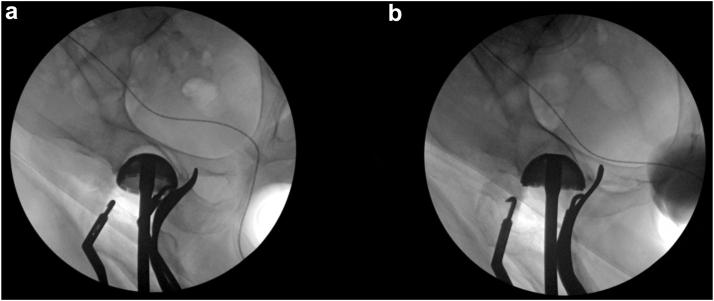

During acetabular cup positioning, intraoperative measurements of cup anteversion were taken using both fluoroscopy and navigation system. With the C-arm introduced at 40°, an anteroposterior view of the pelvis is taken. The C-arm is then centered over the hip, showing an anteverted cup with an approximate inclination of 40°. The axial C-arm is tilted away until the cup opening is visualized as a straight line, indicating that the beam of the fluoroscopy is aligned with the cup's anteversion. The tilt angle on the C-arm and anteversion reading on the navigation workstation were recorded. The high degree of agreement between fluoroscopic and navigation measurement of acetabular cup anteversion supports the use of fluoroscopy in settings with limited access to navigation systems in direct anterior total hip arthroplasty.

在髋臼杯定位过程中,使用荧光透视和导航系统对杯的前倾角进行术中测量。将C形臂以40°引入,拍摄骨盆的前后位片。然后将C形臂置于髋关节上方,显示一个前倾杯,其倾斜度约为40°。轴向C形臂倾斜,直到杯口可视化为一条直线,这表明荧光透视束与杯的前倾角对齐。记录C形臂上的倾斜角度和导航工作站上的前倾角读数。髋臼杯前倾角的荧光透视测量与导航测量之间的高度一致性支持在直接前路全髋关节置换术中,在难以使用导航系统的情况下使用荧光透视。